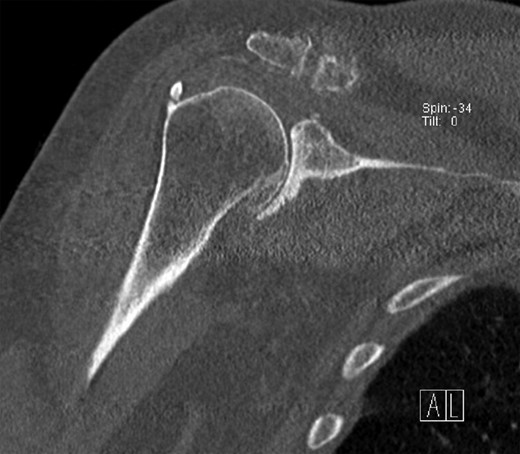

The X-ray and CT scan of the cervical spine revealed significant hyperostosis of the ventral cervical spine segments C3–C7. Hyperostosis was most extensive at segments C3–C5 causing stenosis of the pharyngeal lumen at the level of the larynx (Fig. 1). Due to accompanying joint pain, additional radiological examinations were performed. CT of the right shoulder showed extensive osseous proliferation of the medial humeral head reducing the articular space of the glenohumeral joint, as well as calcification of the rotator cuff (Fig. 2). In the left ankle, the CT scan revealed ossification of the deltoid ligament, and Kellgren grade 4 arthrosis of the tibiotalar and talocalcaneal joints (Fig. 3).

CT of the right shoulder in a coronary plane. Hyperostosis is present at the medial side of the humeral head, as well as at the humeral insertion of the rotator cuff.